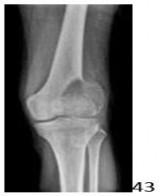

5. # A 21-year-old man has had progressive knee pain and has been limping for the past several weeks. Examination reveals decreased motion, pain, swelling, and marked tenderness over the lateral aspect of the knee. An AP radiograph is shown in Figure 43. Given the radiographic appearance of the lesion, what is the most likely diagnosis?

DISCUSSION: The radiograph shows a lytic, eccentric, expansile lesion of the distal femur that extends to the subchondral surface and has a pathologic fracture. There is no surrounding sclerosis. This is a classic appearance of a giant cell tumor of bone, and the knee is the most common presenting location. None of the other lesions listed have these same characteristics, and typically do not appear in a subchondral location. Chondroblastoma (not a choice) may have a similar appearance, and typically appears in younger patients with open physes. The Preferred Response to Question # 43 is 2.